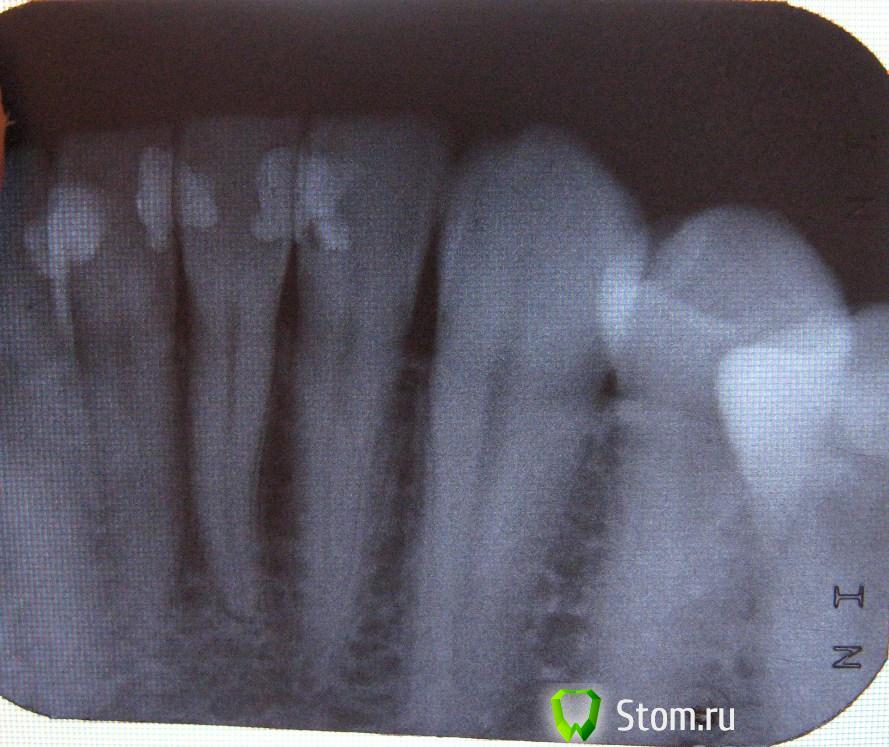

anna78 Опубликовано 13 декабря, 2011 Поделиться Опубликовано 13 декабря, 2011 (изменено) Прокомментируйте снимок, пожалуйста. Особенно волнуют места: между верхушек корней верхних 2-ки и 3-ки справа на снимке (показалось какое-то затемнение), 1-цы и 2-ки внизу околокорневое состояние. Изменено 13 декабря, 2011 пользователем anna78 Ссылка на комментарий

Magdalena Опубликовано 14 декабря, 2011 Поделиться Опубликовано 14 декабря, 2011 (изменено) 1-цы и 2-ки внизу околокорневое состояние. По прицельному снимку можно определить состояние корней только 41, 31, 32 зубов. В области корня 41 зуба все в порядке, в области 32 зуба тоже, но определяется явное нарушение краевого прилегания пломбы, т.е. пломбу необходимо заменить. В области верхушки корня 31 зуба определяется небольшое расширение периодонтальной щели, что может указывать на хроническое воспаление пульпы (нерва) зуба, для исключения необходимо провести электроодонтометрию (ЭОД). Для полноценной диагностики рекомендую сделать компьютерную томограмму (КТ) - по ней можно подробно посмотреть состояние корней всех зубов. Еще бы обратила Ваше внимание на 27 зуб - под пломбой определяется довольно глубокая полость, хотя возможно это просто наложение тени, для точной диагностики - прицельный снимок или опять же, КТ. Изменено 14 декабря, 2011 пользователем Magdalena Ссылка на комментарий